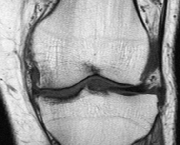

Também conhecida como gonartrose, a osteoartrose do joelho é uma enfermidade degenerativa e inflamatória que resulta na destruição da cartilagem das articulações levando à deformidades nelas. Normalmente a degeneração cartilaginosa começa com o envelhecimento do indivíduo.

De acordo com especialistas a osteoartrose do joelho é uma enfermidade crônica, que afeta as articulações axiais e periféricas que estão relacionadas com mais frequência a sustentação do peso corporal. Possui uma evolução lenta e assintomática. Alguns estudos demonstraram que o problema atinge cerca de cinco por cento das pessoas com menos de trinta anos e cerca de oitenta por cento dos indivíduos com mais de sessenta anos. Uma pesquisa realizada pela OMS (Organização Mundial de Saúde) demonstrou que a osteoartrose de joelho seria uma das principais causas de incapacidades tanto em homens quanto em mulheres. Os estudos radiográficos que foram realizados demonstraram alterações em cerca de trinta por cento em ambos os sexos, com apenas um terço desse total apresentando sintomas.